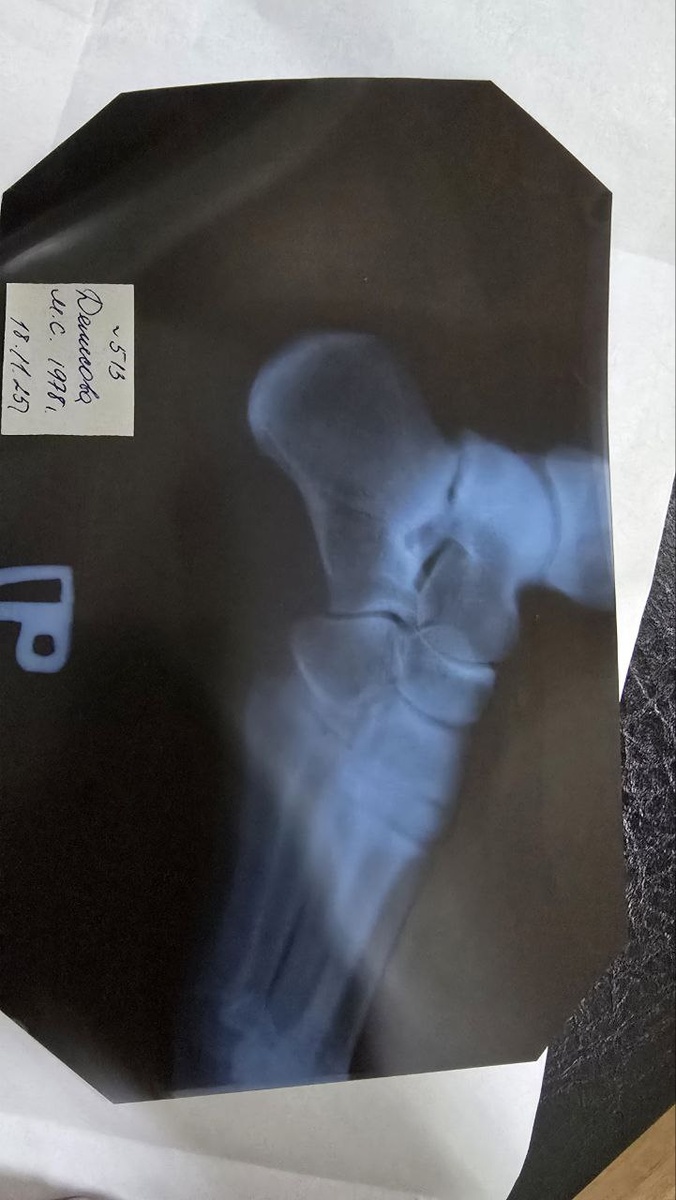

Мой снимок

Мой снимок😊